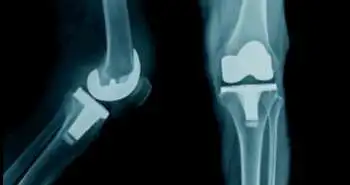

Regional analgesia found effective for mitigating immune suppression after TKR

As per recent research conducted in the Department of Anesthesiology and Intensive Care Medicine, Lovran, Croatia, the postoperative regional analgesia helped to maintain immune system among patients who went through total knee replacement (TKR).

Surgical stress and pain after the surgical treatment initiate a pro-inflammatory response which leads to a decrease in body immunity. The low immunity may enhance postoperative complications like lengthening of wound healing and infections. Two components of cellular immunity; natural killer (NK) cells and T lymphocytes play an essential role in maintaining immunity. Therefore, Sandra Velcic Brumnjak and colleagues attempt to preserve and regain cytotoxic potential of NK cells, NKT cells, T lymphocytes and their sub-populations via three types of postoperative analgesia among patients after TKR. The evaluation of which analgesic approach is more useful to strengthen the immune system was also done.

A total of 40 patients were selected for the analysis. These patients were randomly assigned to three groups. Group one patients obtained epidural analgesia; group two patients obtained femoral and sciatic nerve block and group three received systemic multi-modal analgesia. The pain was measured before, immediately after surgery, 24 h and 72 h post-treatment. At the same time point, blood samples were accumulated for peripheral blood mononuclear cells isolation. Flow cytometry was used to detect and assess NKT, NK and T lymphocytes frequencies along with their perforin expression.

A reduction in severe pain was seen in group 1 and 2 as compared to group 3. also, the NKT, NK and T lymphocytes frequencies along with their perforin expression were considerably higher in group 1 and group 2 as compared to group 3. the group one exhibited better outcomes as compared to other two groups, and this reflects a considerable efficacy of regional epidural anaesthesia.